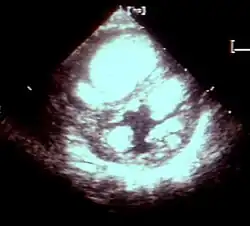

Mięśniak prążkowanokomórkowy (łac. rhabdomyoma, ang. rhabdomyoma) – guzowata zmiana w mięśniu poprzecznie prążkowanym lub mięśniu sercowym, przypuszczalnie o charakterze zaburzenia rozwojowego typu hamartoma, niekiedy określana jako nowotwór łagodny. Mięśniak prążkowanokomórkowy serca jest najczęściej bezobjawowy, objawy mogą wystąpić wskutek zwężenia drogi przepływu krwi. Guzy te nie mają predylekcji do określonej jamy serca i osiągają średnicę do kilku centymetrów. Histologicznie stwierdza się w nich obecność dużych, okrągłych lub wydłużonych komórek z centralnie położonym jądrem i licznymi wakuolami bogatymi w glikogen[2]. Mięśniaki prążkowanokomórkowe serca spotykane są przede wszystkim u niemowląt i mogą samoistnie ustępować; są typowym objawem stwardnienia guzowatego.